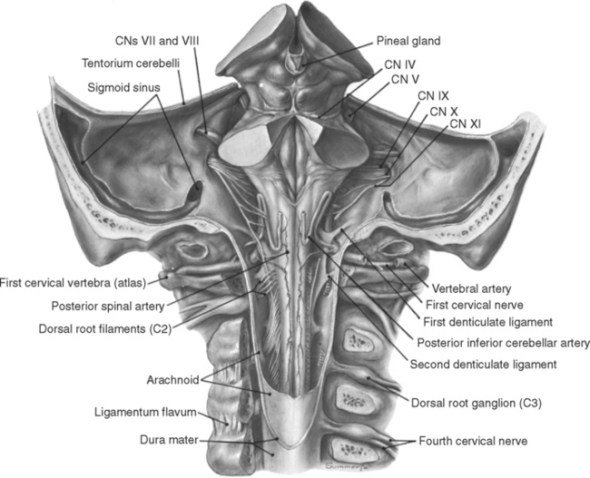

Know your spinal cord – The landmarks

A human cervical spinal cord slice. Once you’ve read this post, you should be able to identify the major parts and tell which side is the front of the cord.

Welcome to day thirty-three in our series. For those of you who are just finding us, we have every one of these posts in our neuroanatomy category in reverse chronological order. Today we’re going to backtract (get it?) a little and go over something basic, but something we’ve skipped over to this point. We never really talked about the landmarks of a spinal cord slice. So today, we are going to take a detour and go over spinal cord features.